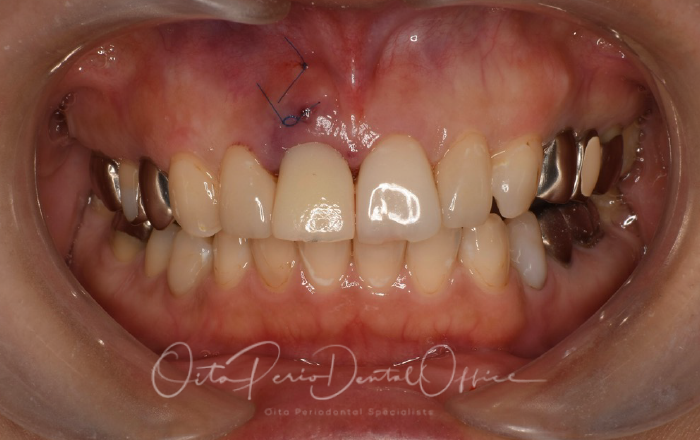

治療後の写真